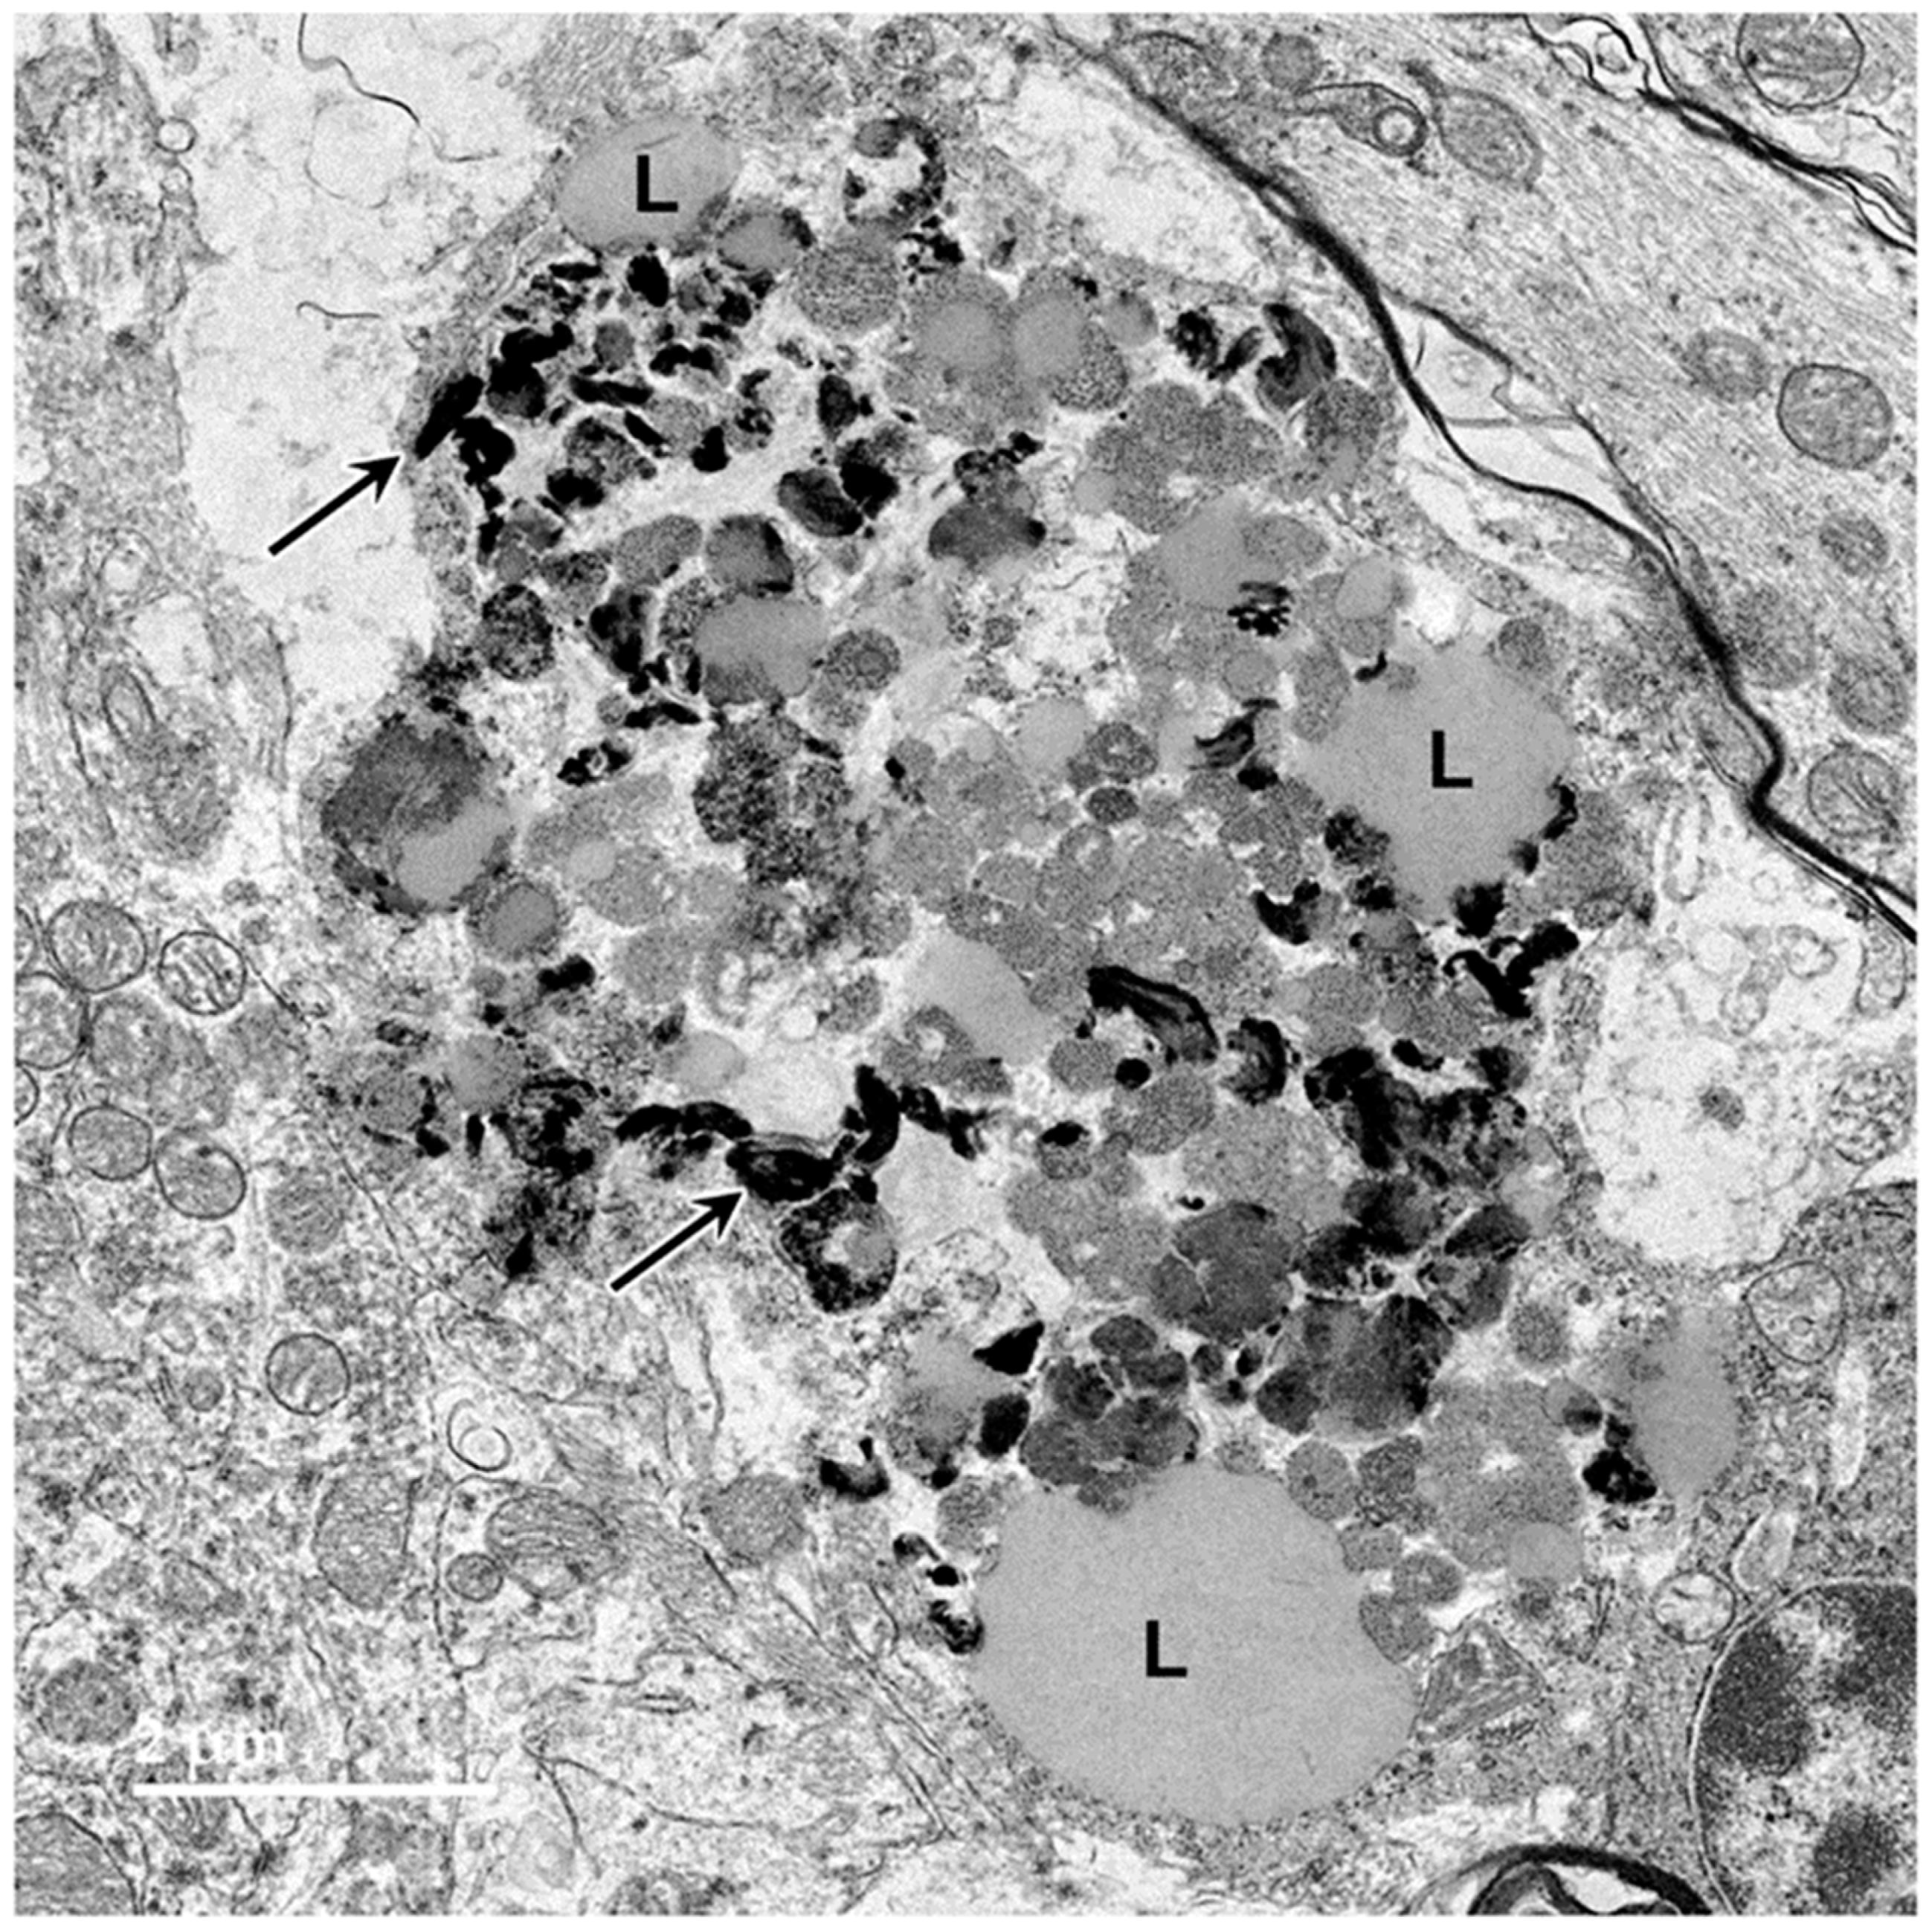

3.1. Microscopic Findings